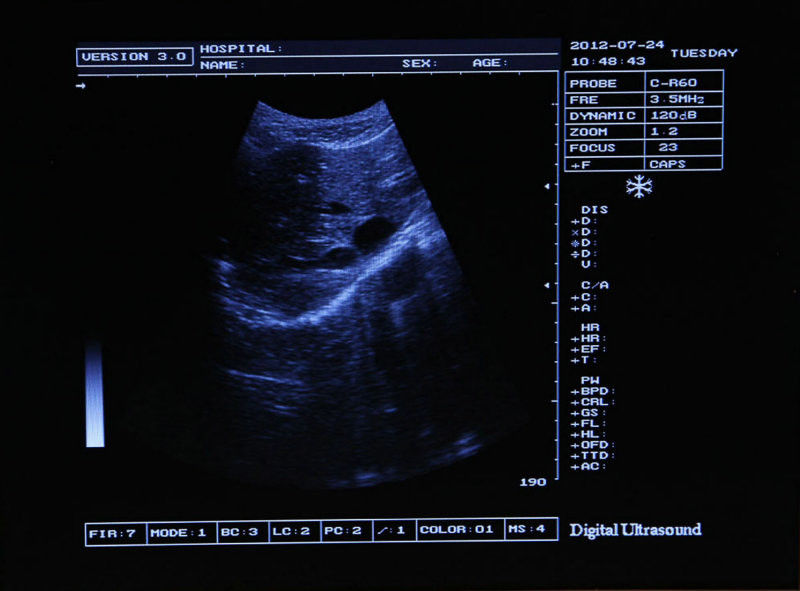

High-Quality Imaging for Accurate Diagnoses

The 12-Inch Carejoy Digital Ultrasound Scanner is designed to provide exceptional image quality, making it easier for healthcare professionals to obtain accurate diagnoses. With its advanced technology, the ultrasound scanner ensures that the images produced are clear and detailed. This is crucial for monitoring patient health and diagnosing conditions effectively. Because of this, clinicians can feel confident in their evaluations and treatment plans.